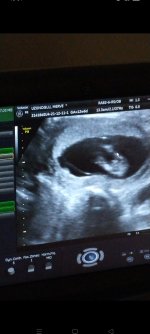

Erkek canım benim oğlumun da ultrasonu böyleydi. Ne gibi bişey hissedeceksin ki ? Belirtileri vs diyorsan kişiden kişiye göre değişir o cinsiyetle alakası yok

Bilmiyorum ki hamileliğim çok farklı sanki değişecek gibi geliyor önceki bebeğim kış ultrasonu yorumlayamıyorum🤭

Aslında detaylı ultrasona kadar annelerin kesin gözüyle bakmaması gerekiyor ama dediğim gibi ben 17. Haftada öğrendim benimkininde ultrasonu böyleydi